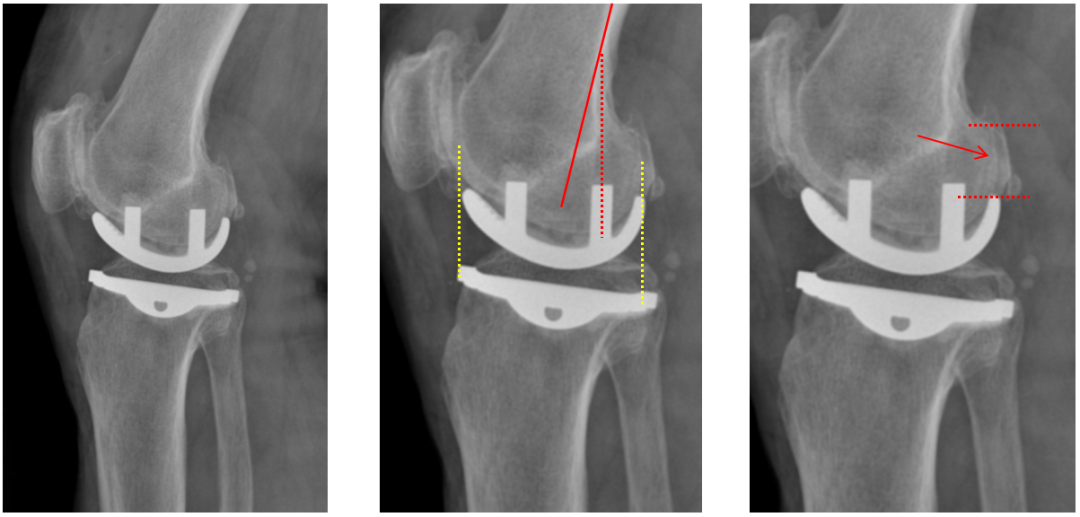

假体位置分析

正位片标准胫骨和股骨假体位置

AP位假体位置:胫骨假体轻度外翻,外侧缘与胫骨平台外侧缘齐平; 股骨假体长轴与胫骨假体垂直,与胫骨假体中线一致。

侧位片标准胫骨和股骨假体位置

侧位片假体位置:股骨假体后倾38°,假体后缘与股骨后髁齐平,胫骨假体后倾3°,与胫骨平台前后缘齐平。

标准胫骨和股骨假体位置

胫骨假体厚度合适

胫骨垫片厚度合适:术前外翻畸形基本矫正,残留2-3°外翻

胫骨假体后倾角度大

侧位片胫骨假体位置:胫骨假体后倾15°,前后缘齐平。

股骨假体偏小

侧位片股骨假体位置:股骨假体偏小,与胫骨假体后缘不齐平;屈曲35°,未包容股骨后髁。

股骨假体偏内放置

AP位胫骨与股骨假体位置:股骨假体中轴线与胫骨假体中线不一致,偏内侧,且外翻。

股骨假体偏外放置

AP位胫骨与股骨假体位置:股骨假体中轴线与胫骨假体中线不一致,偏外侧,且内翻

矫正不足、矫枉过正